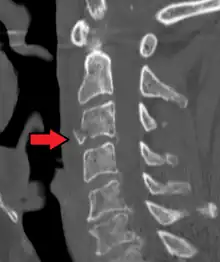

A fracture of the base of the dens (a part of C2) as seen on CT.